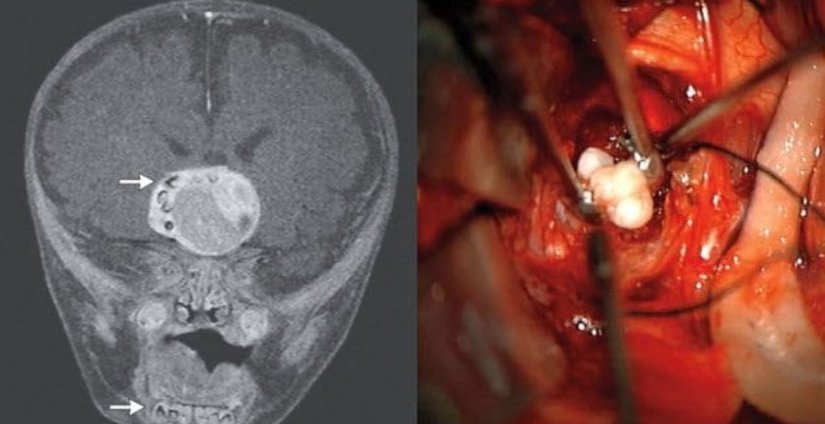

4 aylık bebeğinin normalden daha hızlı büyüyen kafatası ailenin dikkatini çekmesini takiben doktora başvurduklarında, uzmanlar kraniofarinjiyomadan (bir tür beyin tümöründen) şüphelendi. MRI ile incelenen tümör yapısının içerisinde düzenli kalsifiye yapı izlendi. Operasyon anına kadar bu kalsifiye yapının diş olduğu bilinmiyordu. Tümör uzaklaştırıldıktan sonra bebek sağlığına kavuştu. Fakat 2014 yılında yayımlanan bu vaka raporu ilk defa pediatrik popülasyona ait bir bireyde beyin tümörüne eşlik eden diş ektopisi (ektopi: bir doku/ organın olması gerekenden farklı bir yerde, konumda, pozisyonda olması) olarak büyük ses getirdi.